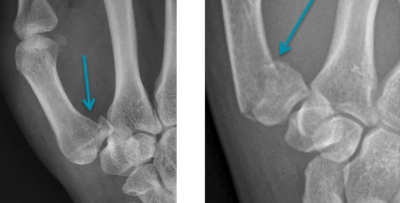

Fracture de Rolando / Fracture de Benett

La radiographie réalisée met en évidence la fracture. La radiographie permet de localiser la fracture en différenciant fracture articulaire multi-fragmentaire (fracture de Rolando) d’une fracture articulaire simple (fracture de Benett).